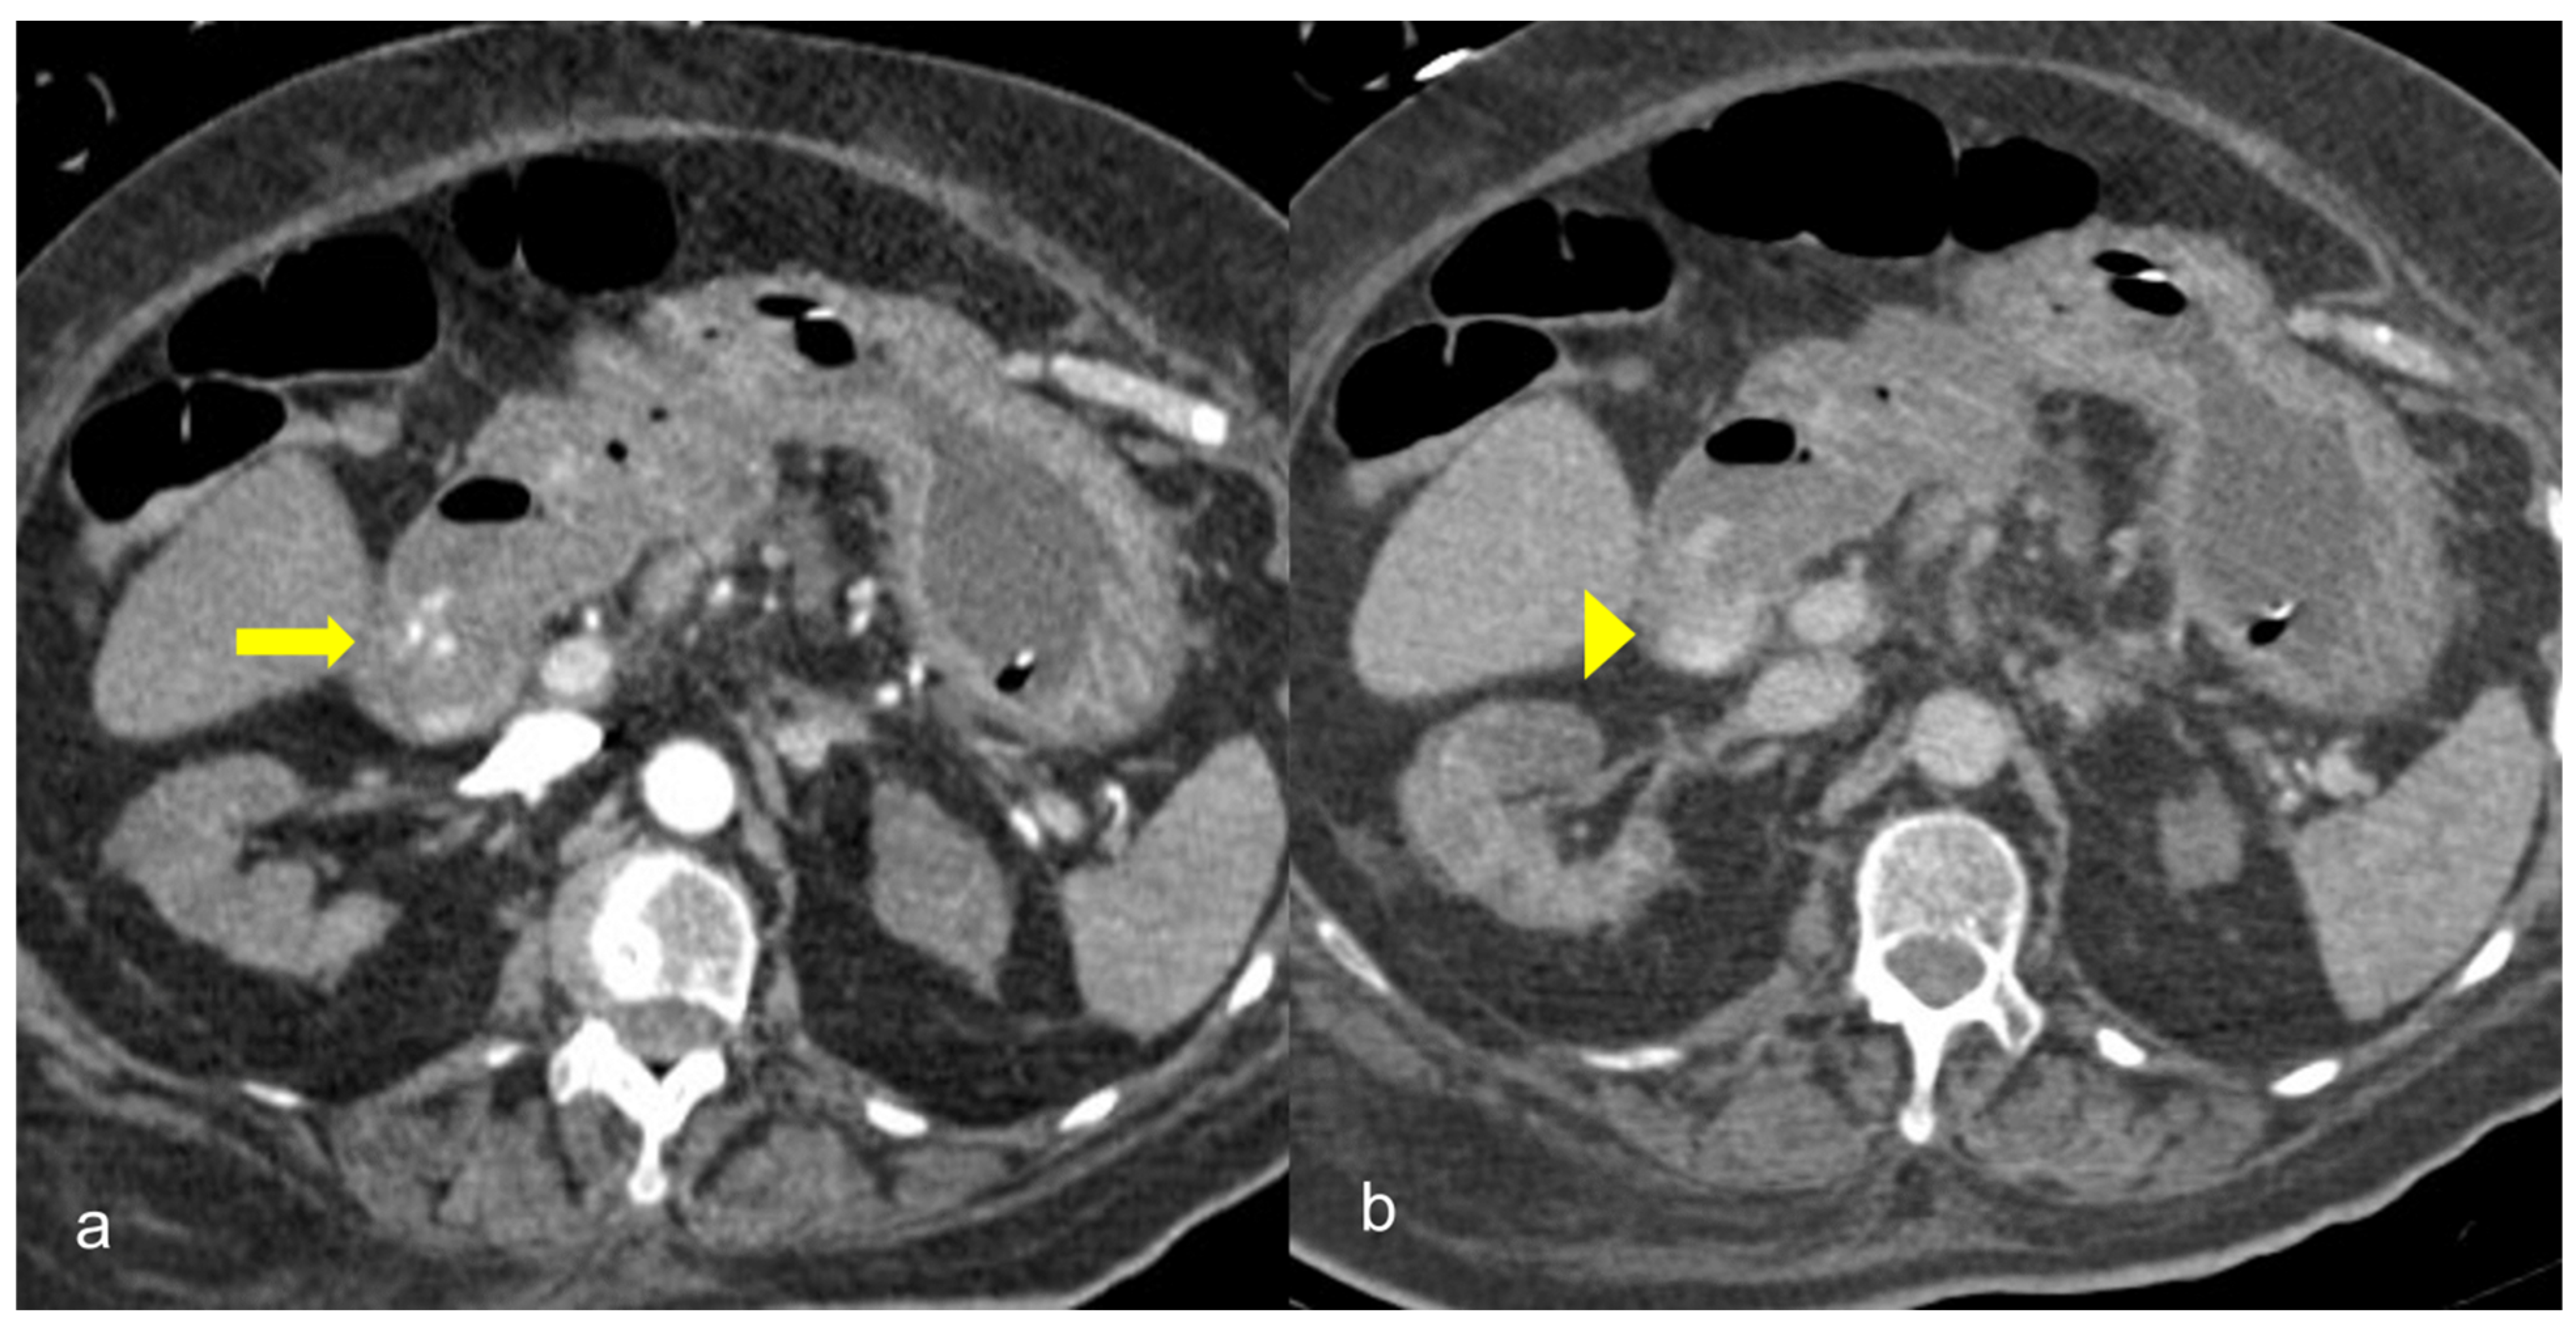

Figure 9. 81-year-old patient with COVID-19 pneumonia developed epigastric pain at the second day of hospitalization. CT demonstrating acute pancreatitis (yellow arrow).

The temporal relationship between the onset of COVID-19 infection and inflammation of the pancreas has not been clearly established. Some patients develop COVID-19 symptoms and abdominal pain when the infection begins, whereas others present with AP several days after COVID-19 diagnosis (Figure 9) [37].

A study of 52 patients with COVID-19 pneumonia showed that there was a 17% incidence of pancreatic injury. Kumar V. et al. studied patients with acute pancreatitis and COVID-19 infection and found that half of them developed AP after a median of 22.5 days from the onset of respiratory symptoms, while the rest of them were admitted for abdominal pain [38] Another systematic review, including overall 37 patients, summarized that AP might be the first symptom of COVID-19 [39]. In addition, COVID-19 may negatively influence the morbidity and mortality linked with AP [40].